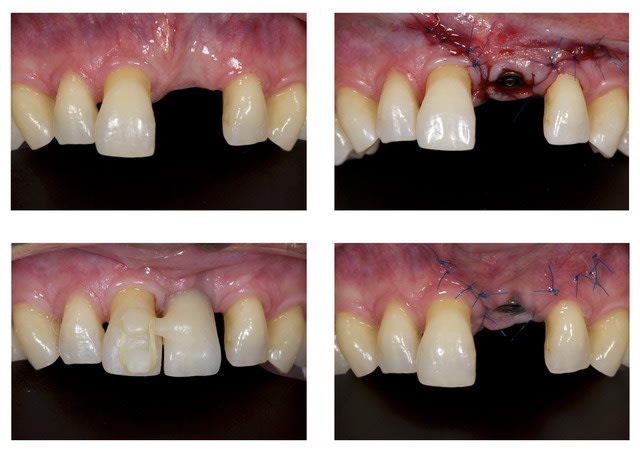

07/11/2013 à 13h07

Le cas est terminé mais je ferai la photo finale lors du prochain controle.

Sans titre   copie cnlkjz - Eugenol

05/08/2014 à 11h23

Comme demandé en MP voici le contrôle 10 mois après la pose.

C'est acceptable je pense. Ce traitement a ses limite bien sûr mais peut être une indication voire une alternative dans certains cas spécifiques comme celui-ci.

Au passage, qui connait le nom que l'on donne à cette collerette de GA que l'on voit sur 13-12-11-22-23, j'ai oublié.

A omtjjz - Eugenol

1 zf3owi - Eugenol

Img 0812 mvp6i0 - Eugenol

jeamba

05/08/2014 à 20h20

Je ne sais pas si tu as réellement ingressé car quad je regarde ta radio du départ et celle que tu viens de mettre, ton apex arrive pratiquement au même niveau de spire, à savoir au niveau de la troisième spire en partant de l'apex de l'implant. Il y a quelque chose qui m'échappe.

Img 1744 z0evts - Eugenol